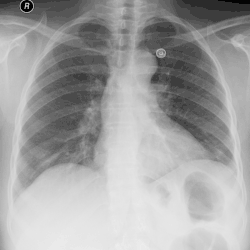

A massive left pleural effusion displacing the heart and trachea to the right

A pleural effusion is an accumulation of fluid inside the pleural space. If this collection of fluid gets large enough, it can also push structures in the chest away from it and cause a mediastinal shift. However, a pleural effusion can also pull the mediastinal structure towards itself. If this is the case, then there is an underlying condition causing the collapse of the lung on that side. An example is a tumor obstructing a bronchus and causing lung collapse and pleural effusion.[3]